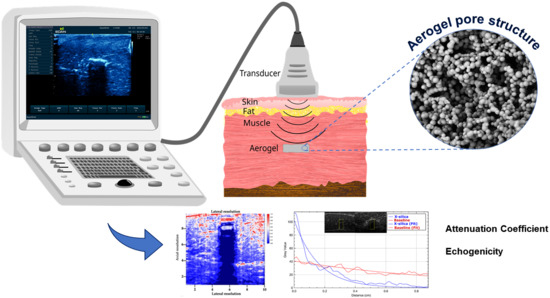

Noninvasive Detection, Tracking, and Characterization of Aerogel Implants Using Diagnostic Ultrasound

:1. Introduction

3.3. B-Mode Images

3.5. Echogenicity

4.1. Ultrasonography and Aerogel Dimensional Analyis